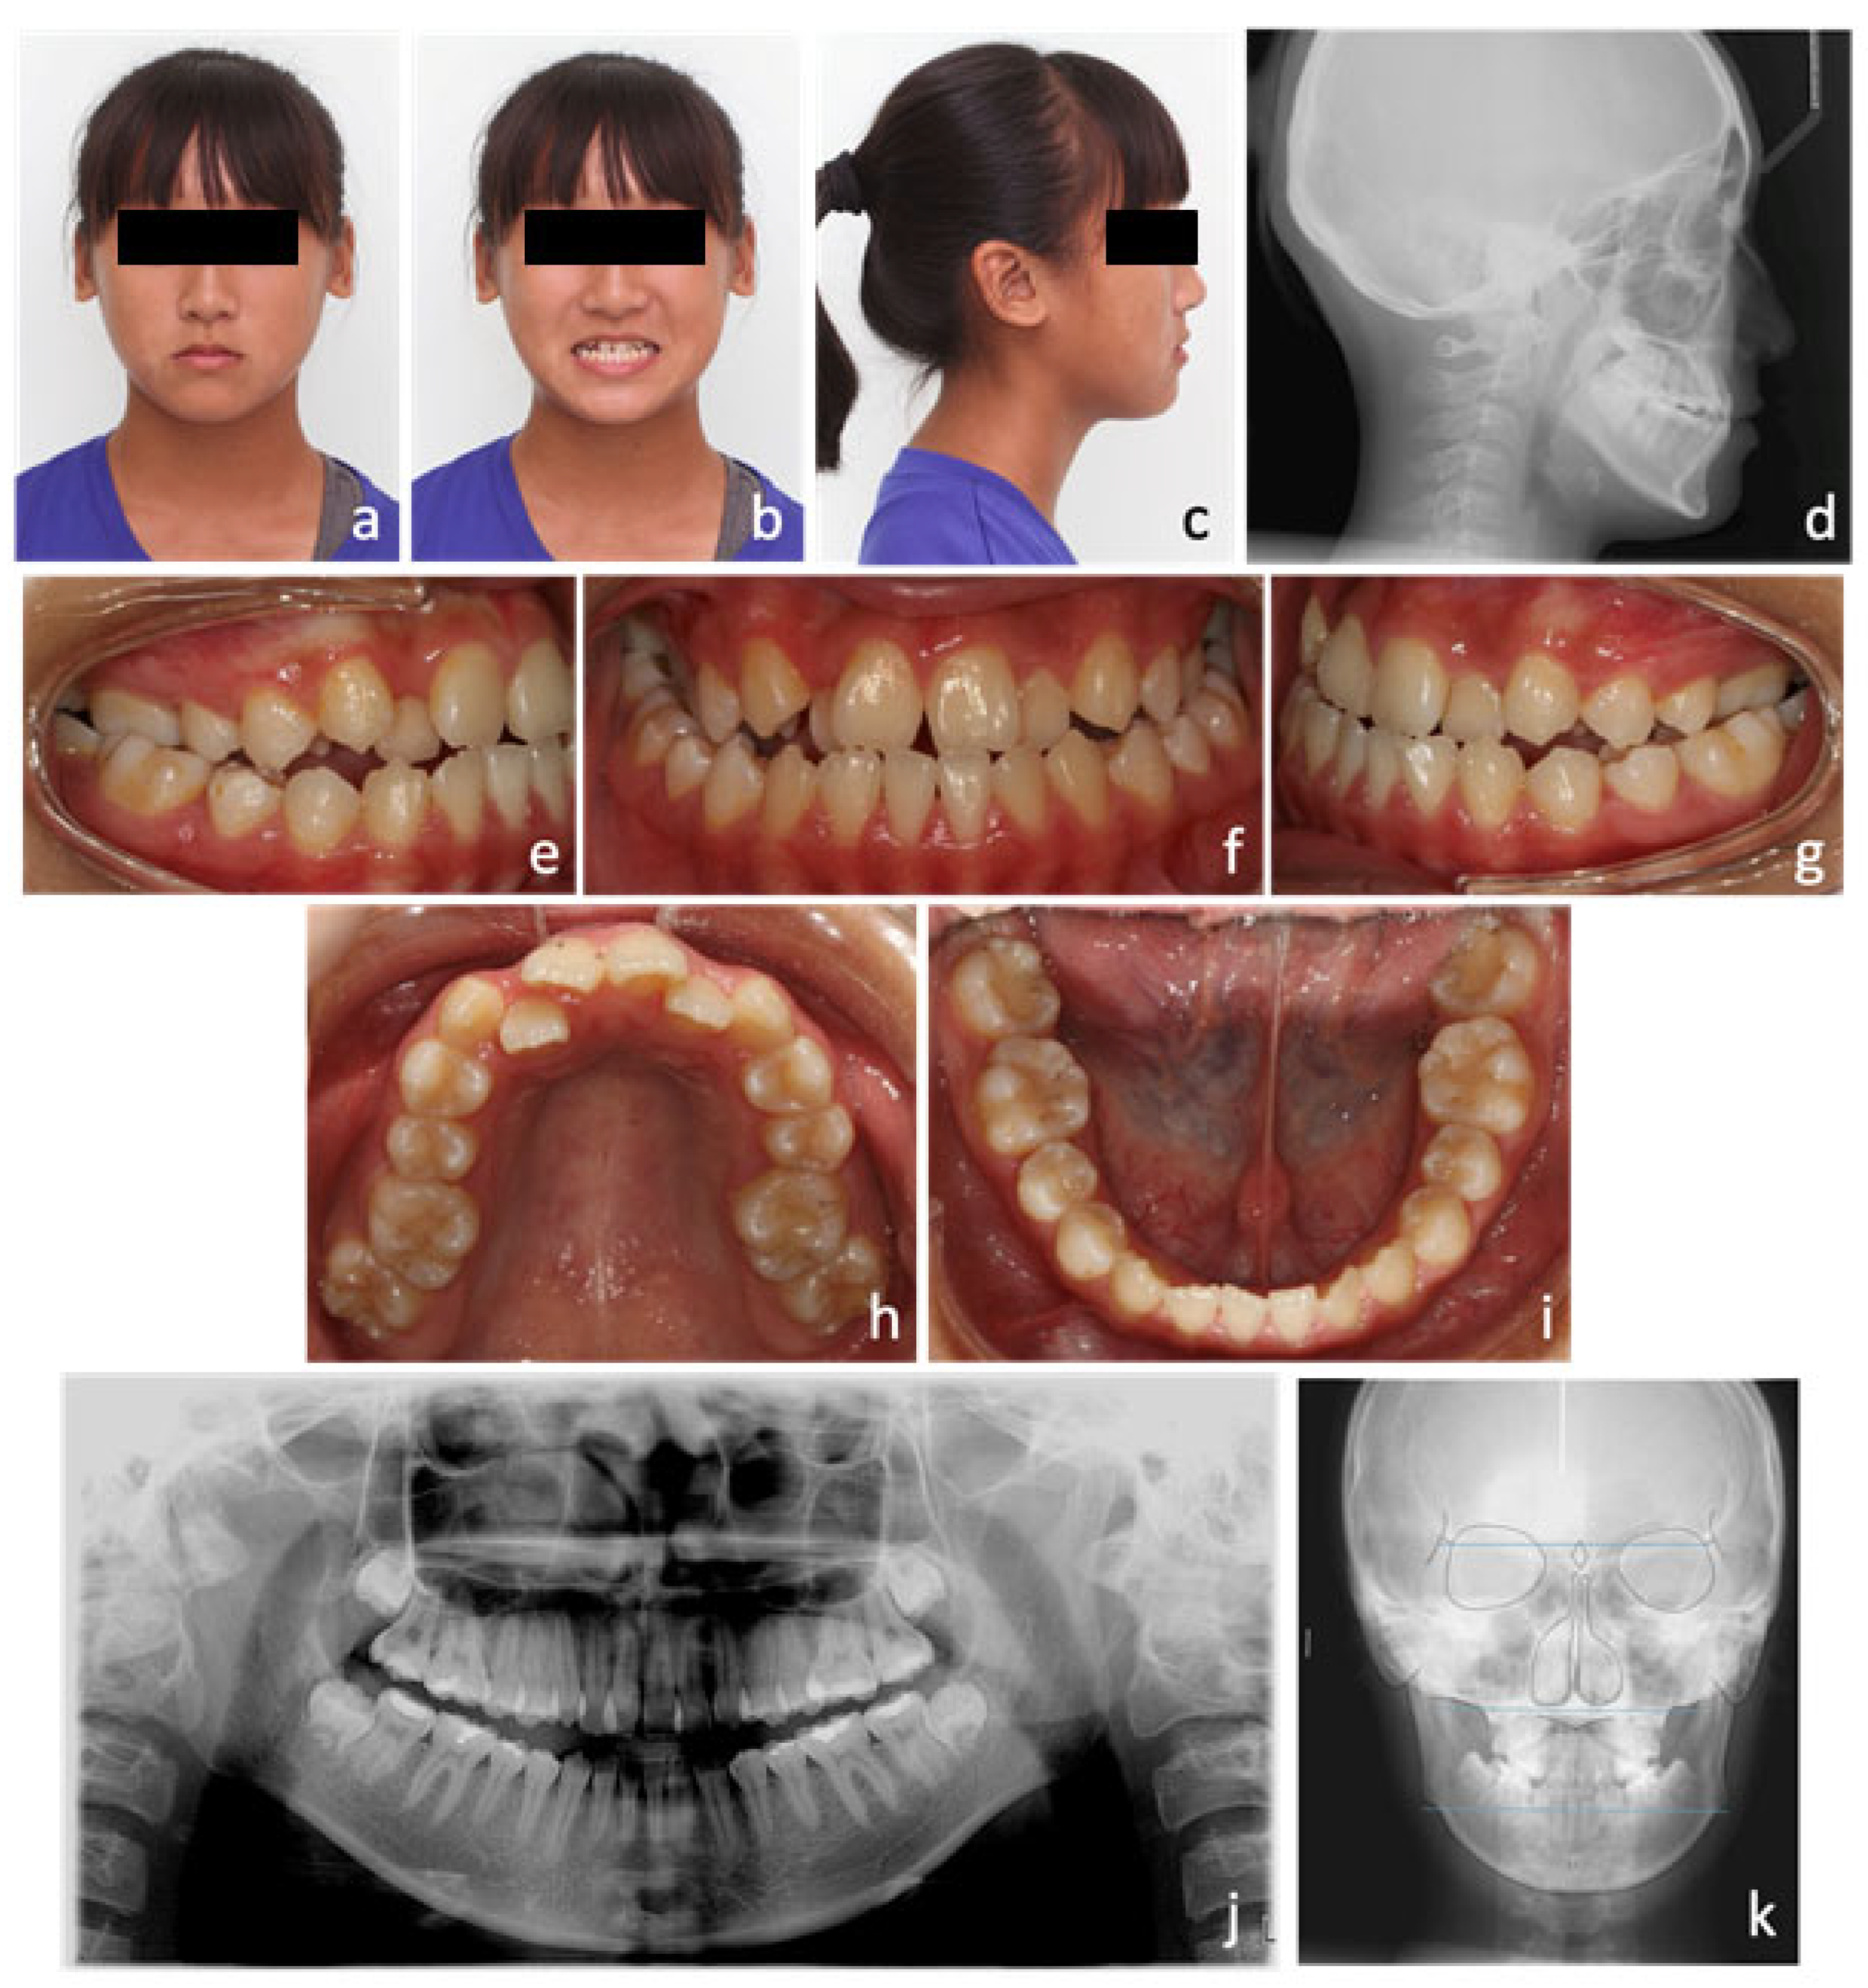

2. Case Report

2.1. Diagnosis and Aetiology